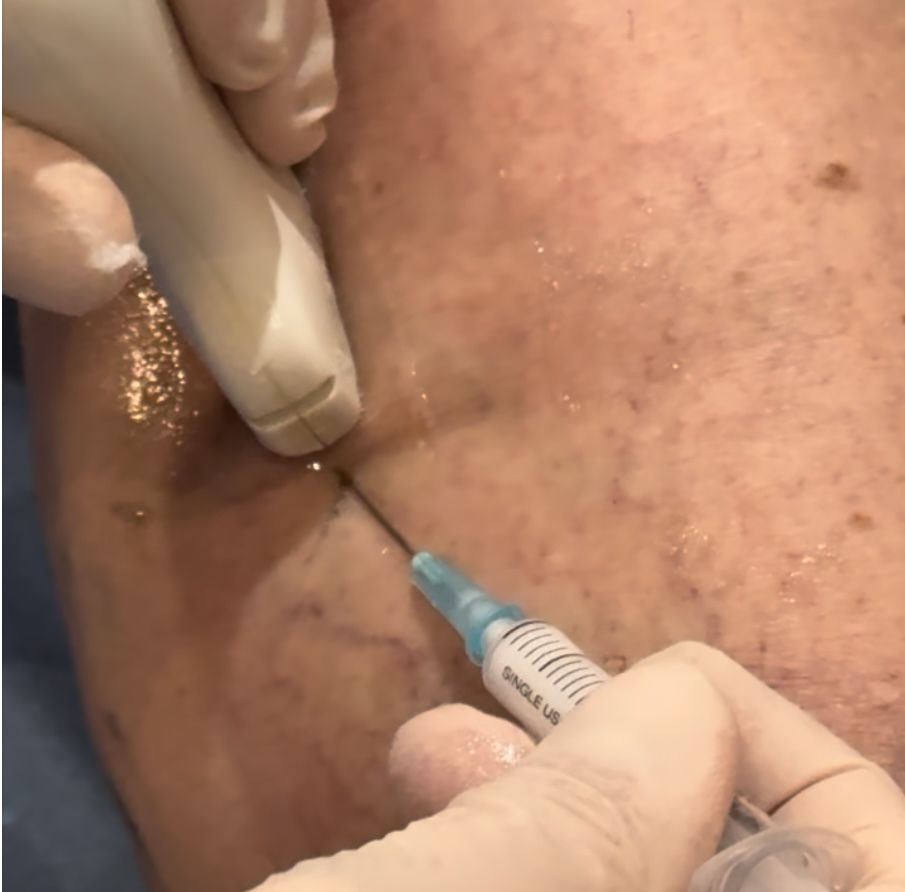

Sclérothérapie échoguidée à la mousse

La sclérothérapie échoguidée à la mousse (SEM)

Traitement sans chirurgie et sans anesthésie

Cette méthode offre une solution efficace et confortable pour traiter les veines variqueuses avec des résultats durables

La microsclérose

La microsclérose est le traitement de choix des varicosités.